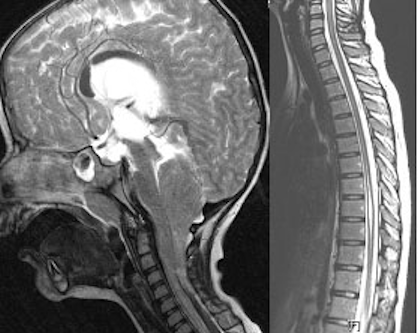

Diese Erkrankungen führen zu einer dringlichen rekonstruktiven Operationsindikation innerhalb des ersten Lebenstages, um eine Deckung der Hüllen des Rückenmarkes mit seinem Liquorraum zu erreichen und die Infektionsgefahr einzuschränken. Die okkulten Dysraphien (Spina bifida occulta) beinhalten komplexe Fehlbildungen wie den dorsalen Dermalsinus, die Myelomeningozele (MMC) die Lipomeningomyelozele, das sekundäre Tethered Cord Syndrom, die Diastematomyelie und häufig die Hydrosyringomyelie. Die Häufigkeiten haben in den letzten Jahren glücklicherweise stark abgenommen, da der Zusammenhang mit der Folsäureaufnahme sinnvoll erkannt wurde. So gibt es in Großbritannien etwa 1.200 Schwangerschaften im Jahr mit Dysraphie, davon werden etwa 200 ausgetragen. Ein Teil des Rückgangs der Geburten mit Spina bifida ist durch den heute häufigeren Schwangerschaftsabbruch zu erklären. Durch die Berücksichtigung des Folsäurestatus und entsprechend frühzeitiger Substitution konnte in Ländern mit Nahrungsanreicherung die Prävalenz um fast 50% verringert werden. In Deutschland gibt es bis heute keine globale Nahrungsanreicherung mit Folsäure, etwa im Mehl, wie das in Frankreich durchgeführt wird. Ein weiteres kongenitales Krankheitsbild ist die Chiari-Malformation mit einer Kombination aus veränderter Architektur der hinteren Schädelgrube, einem unterschiedlich ausgeprägten Tonsillen- und Vermistiefstand, einem begleitend auftretenden Hydrozephalus und einer manchmal kombinierten Syringomyelie. Bei diesen Kindern entsteht häufig eine ganze Reihe von rekonstruktiven Indikationen zur Dekompression der Medulla oblongata und der hinteren Schädelgrube, zur Therapie des Hydrozephalus und der Syringomyelie (Abbildung 2 [Abb. 2]).

Abbildung 2: Tonsillentiefstand bis HWK 5 bei Chiari Malformation mit Hydrozephalus (links) und beginnender Syringomyelie in Höhe der BWS